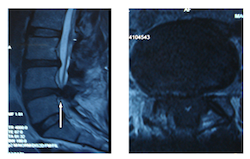

Lomber MR tetkikinde L4-5 mesafesinde fıtık,ligamantum flavum ve faset eklem büyümesine bağlı omurga kanalındaki daralma nedeniyle içinden geçen omurilik ve sinirlerin sıkışmış olduğu görülmektedir.